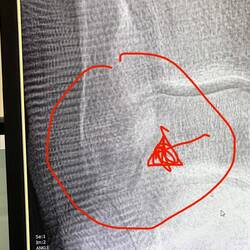

Gerade als ich bei der Beifahrer-Schiebetüre aussteige, beide Krücken rechts, drehe ich mich kurz am Stand und da Alex mit Schwung die Schiebetüre schließt, ist dort auf einmal mein Ellenbogen drin.

Es schmerzt so furchtbar, das ich im ersten Schock weg von der Tür humple, das Blut schießt nur so aus der Wunde. Dann setzt mich Alex wieder in den Schiebetüreingang. Mir wird so schwindelig, vor Blut und Schmerz, das ich mich auf den Boden neben der Schiebetüre hinlegen muss. Erst jetzt kann ich Alex ein paar Anweisungen geben, denn er ist ziemlich aufgeregt und macht sich totale Vorwürfe.

Sensibilisiert, wie ich derzeit bin, will ich ins nächste Krankenhaus. Ich will wissen, ob mein Ellenbogen noch ganz ist.

Es dauert 3 Stunden bis ich das Röntgen bekomme, 2 junge Ärzte sich die Stelle ansehen, ich dann nochmals in den ER-Raum von einem netten Pfleger gefahren werden und dort erfahre das nichts gebrochen ist. Meine Wunde wird noch sehr gut gewaschen und desinfisziert, Verband drum rum und nachdem ich Schmerzmittel und 5-tägige Antibiotikakur verweigert habe, werde ich endlich entlassen.